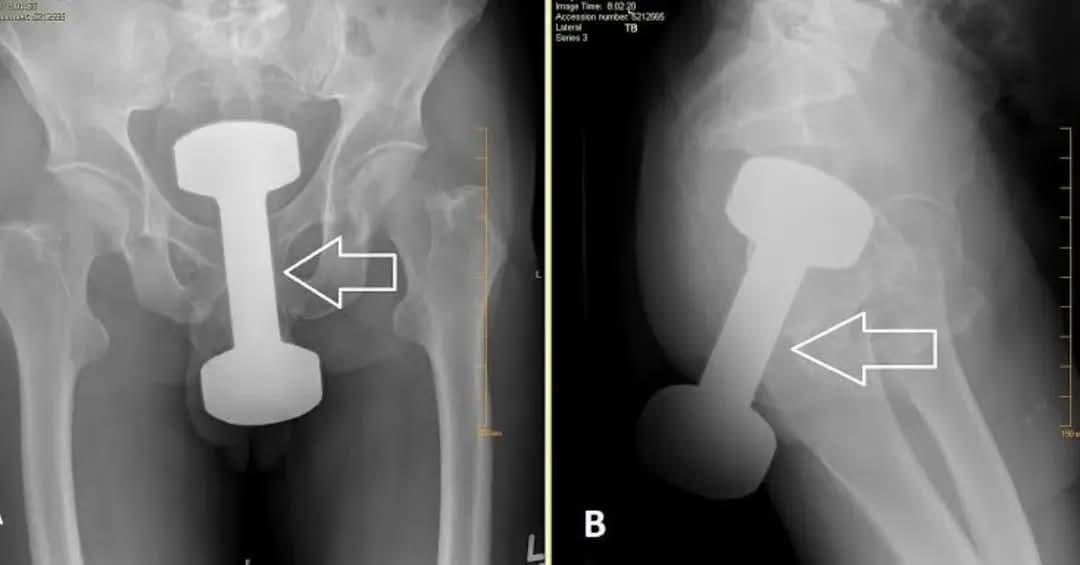

A full metal dumbbell was lodged deep inside a 25-year-old woman’s pelvis. Not a rumor. Not edited. Real hospital imaging reviewed by medical staff who could hardly believe what they were seeing. Surgeons later described the removal as “extremely delicate,” given how dangerously close the object was to major blood vessels and vital organs.

She arrived at the hospital in severe pain. She had a high fever and could barely walk. What initially presented as abdominal distress quickly escalated into an emergency unlike anything the team on duty expected that day. Within hours, she was in surgery. The operating room shifted from routine urgency to intense precision. Every movement mattered. One wrong shift could have caused catastrophic internal damage.